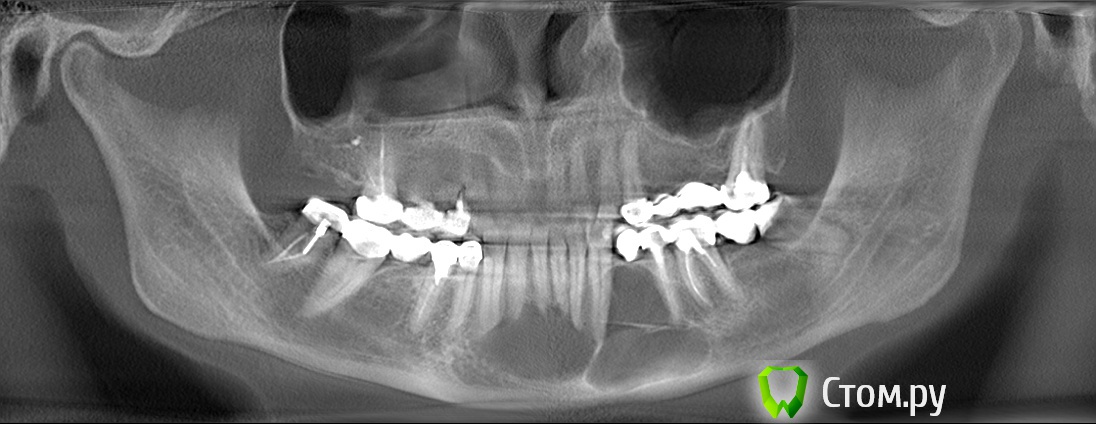

Helenka Опубликовано 23 сентября, 2014 Автор Поделиться Опубликовано 23 сентября, 2014 Сделайте (первый шаг) КТ, покажите доктору, выложите КТ на форум , это займёт , думаю, день-два, что не критично. Сделала КТ, врач сказала что мне уже надо думать о челюсти, а не о зубах. Напугала. Думаю, теперь вопрос стоит по другому - Куда бежать делать операцию? Уважаемые специалисты, подскажите, пожалуйста, где найти врача, который лечит такое намного чаще, чем раз в месяц. С программой на диске не справилась, нашла только один jpg, небольшого размера. Сам диск 500 мб. Ссылка на комментарий

Alexey Doc Опубликовано 24 сентября, 2014 Поделиться Опубликовано 24 сентября, 2014 Судя по рентгенологической картине это вряд ли радикулярная киста. Поэтому вам для начала нужно определиться с точным диагнозом! Для этого нужны результаты гистологического исследования оболочки данного образования. 1 Ссылка на комментарий